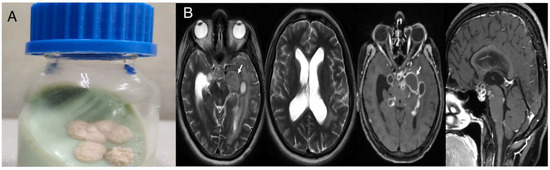

Introduction: Infective endocarditis (IE) is a disease that may frequently lead to significant morbidity and is associated with high mortality rates. Even though IE is classically caused by Gram-positive bacteria, Gram-negative bacteria may seldom ca...